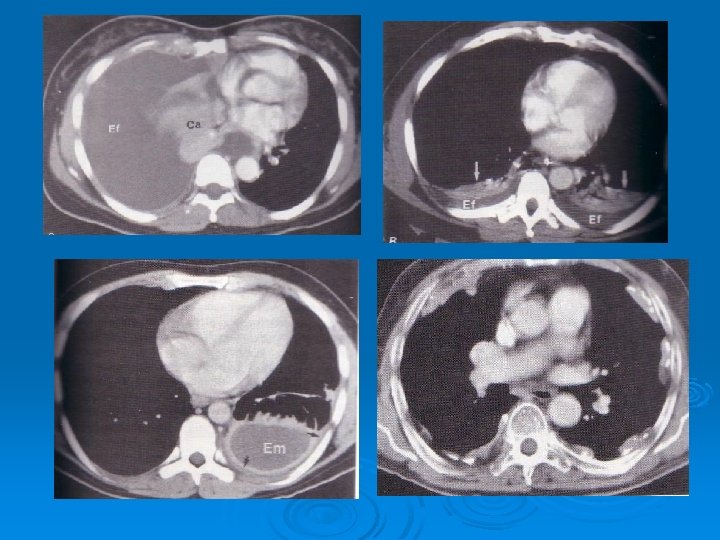

Ø Ultrasound is able to demonstrate smaller amounts of fluid as 100 ml Ø CT has similar sensitivity to ultrasound, not routine but can be performed to evaluate concomitant paranchymal lesions Ø CT is sensitive in identifying pleural thickening and calcification

Ø The most common clinical presentations are dyspnea, chest pain, unilateral decreased volume of the affected hemithorax (frozen chest) (inspite of fluid accumilation) Ø Nodular thickening of the pleura, irregular thickening of the interlobar fissure, absence of mediastinal shift with massive pleural effusion (frozen chest) Diagnosis by histologic examination Ø Treatment oncologic and surgical if possible, prognosis is poor Ø